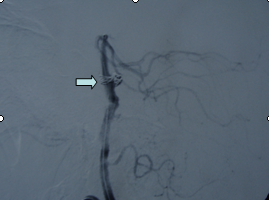

吴某,56岁,因突发昏迷1小时于2月15日急诊入院。入院时深昏迷,呼吸微弱,血氧和血压降低,双侧瞳孔散大,对光反射迟钝,急诊头颅CT提示蛛网膜下腔出血。入院诊断考虑是脑动脉瘤破裂,紧急行气管插管、止血降颅压等抢救措施,同时放射科陆秀伟主任急诊行全脑血管造影,结果提示基底动脉巨大的动脉瘤(图一)。科主任范学政教授紧急组织全院会诊,组成了包括神经外科、重症医学科、呼吸科、放射科专家抢救小组,采取镇静、脱水、抗血管痉挛以及支持和对症等抢救措施,并病情和影像资料传输到神经外科协助医院四川大学华西医院神经外科远程会诊,会诊认为该病人最佳的治疗方案是行血管内介入治疗。经过充分准备,于2月19日在华西医院神经外科张昌伟教授联合我院神经外科医生为患者进行了支架辅助下基底动脉瘤弹簧圈栓塞术,术后行脑血管造影显示动脉瘤完全栓塞(图二)。术后继续予抗血管痉挛等治疗,术后第二天出现呼吸衰竭,肺部感染,后经转入ICU、呼吸科、予以支持、抗感染治疗等综合治疗,术后10天病人清醒,目前患者已经康复出院。

图2:动脉瘤介入栓塞后